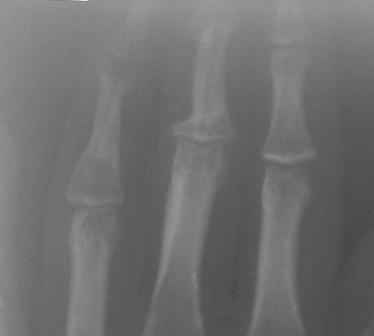

Уважаемые коллеги, на осмотре девочка 2006 г.рожд. Со слов матери 3мес. назад заметила припухлость основного фаланга 3-пальца, которая постепенно увеличилось до настоящего размера где-то в течении месяца, не болит, ребенка не беспокоит, признаки воспаления отсутствуют. Консультация онколога, биопсия - опухоль исключена (со слов матери), фтизиоортопед - тбс исключен. От основной фаланги 3 пальца к головке 4-пястной кости под кожей прощупывается хрящевидная ткань. Р-граммы от 10 декабря и 15 февраля, и фото прилагается. Что делать? Уважаемые коллеги, помогите! С уважением Абдурашид.

Добрый день, уважаемый Абдурашид. Судя по рентгенограмме, к сожалению не очень качественной, речь может идти о варианте дисхондроплазии, которую обозначают, как солитарную хондрому. Рентгенологически они проявляются в 3 вариантах-в виде интрамедуллярно и центрально расположенной энхондромы с вертеннобразным вздутием диафиза изнутри и истончением кортикальной пластинки, в виде опухоли, расположенной эксцентрично с заполнением части кортикального слоя и характерным костным козырьком, в виде экхондром, выступающих за пределы кости